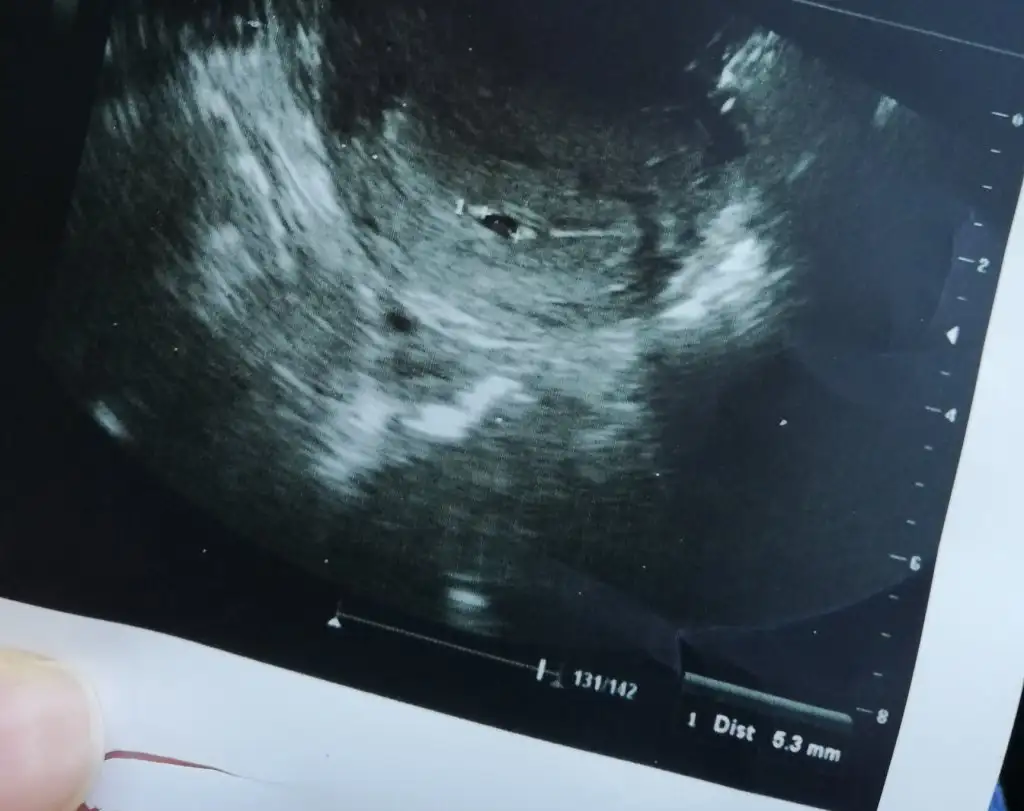

Merhaba benimde kan pıhtılaşmam var sanırım kanama alanım var usg de çıkmış ama doktor bişey demedi kan sulandırıcı kullanıyorum kan sulandırıcı tetiklemez mi?

• IMG_20221031_125226.webp

IMG_20221031_125226.webp

25,8 KB · Görüntüleme: 174